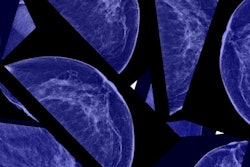

Radiation dose-tracking software developer Imalogix has received a contract from group purchasing organization Premier.

The deal, which became effective July 1, provides Premier members with special pricing and terms for the company's cloud-based imaging performance management and dose monitoring software, Imalogix said.